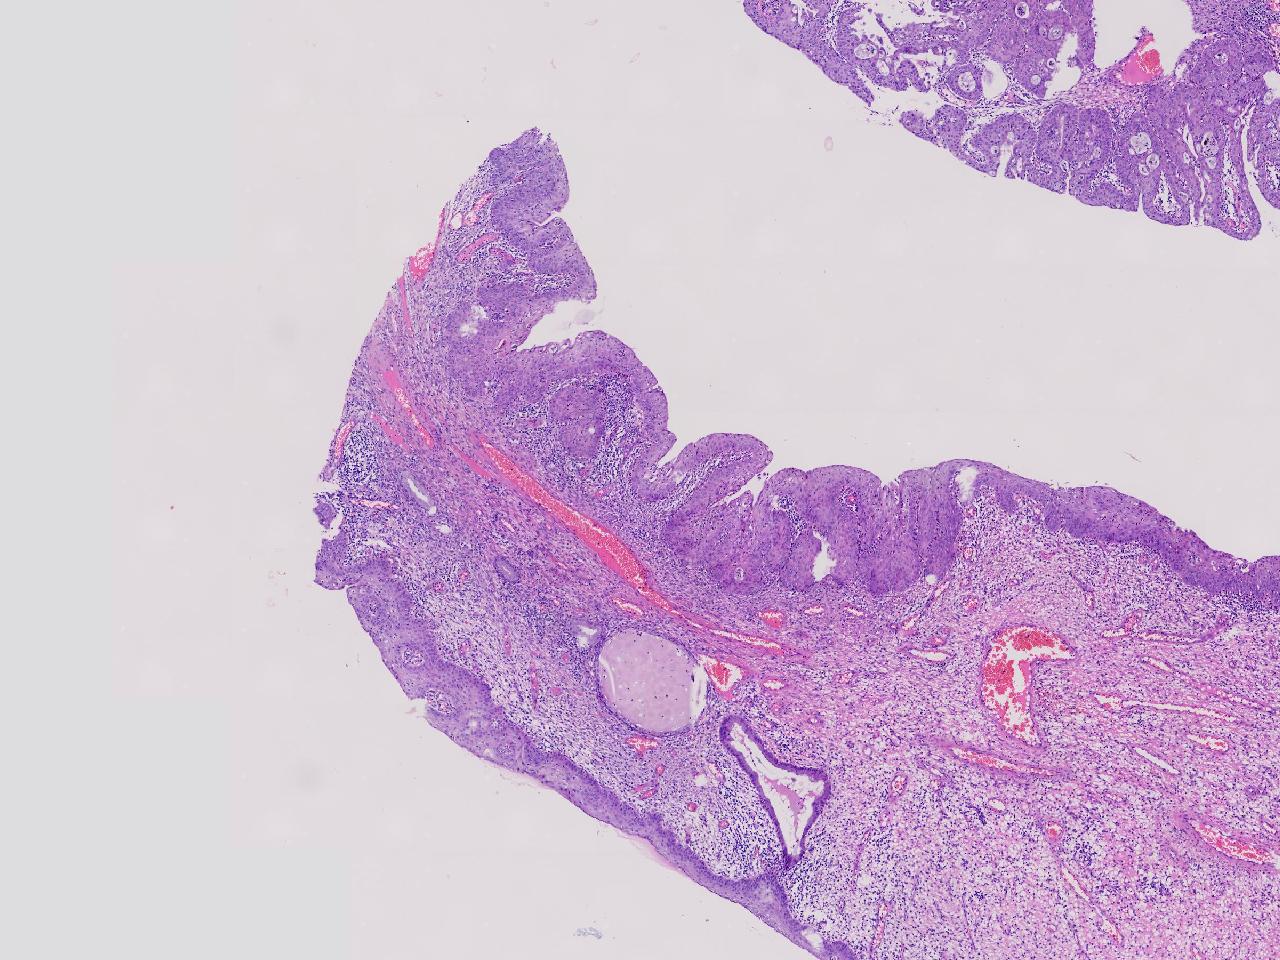

性别年龄42岁临床诊断宫颈赘生物

一般病史女,42岁,妇检时发现宫颈赘生物,大小0.2cmx0.5cm

标本名称管状赘生物

大体所见灰白色不整形软组织2块,一个直径0.3厘米,一个直径0.2厘米。

炎症

低级别诊断需要有个尺子,这个尺子就是“似是而非为非”,这个连似是而非都达不到。

有非典型鳞化,建议HPV检测

慢性宫颈炎伴腺上皮鳞化。